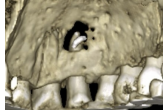

Colocación de implantes en 34 y 36 con ROG simultánea